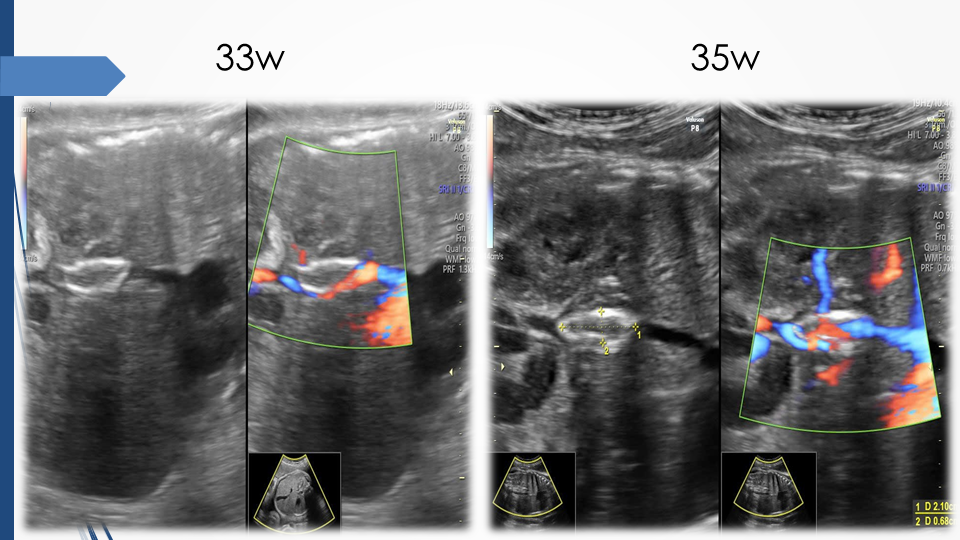

Tầm soát chủ động bất thường dây rốn và tuần hoàn thai để giảm thiểu nguy cơ thai lưu đột ngột - Báo cáo loạt ca hiếm gặp và khuyến nghị thực hành